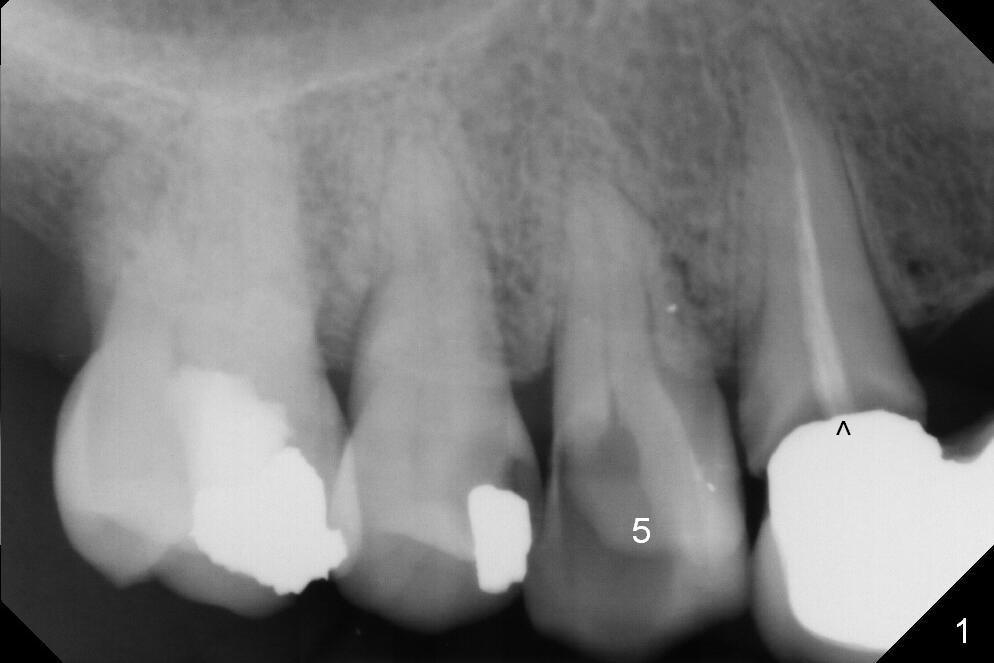

A 43-year-old woman has poor dentition including the tooth #5 (Fig.1) for RCT (Fig.3) and the teeth #2, 30 and 31 are missing. The retainer at #6 fractures (Fig.1 *). After sectioning the bridge between #7 and 8, fabricate prefabricated post at #6 if the latter is salvageable. Otherwise extract (Clindamycin) and implant (Fig.3). Anyway, a 3-mm or smaller one-piece implant is to be placed at #7 for stability and retention. Pay attention to the labial concavity at #7 (Fig.2 *). Surgical stent has been made.